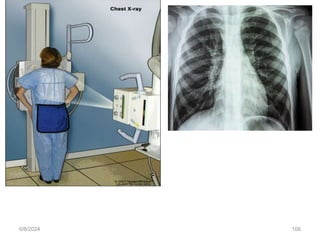

Diagnostic evaluation- Cont’d- imaging

• Chest X-Ray

• Normal pulmonary tissue is radiolucent; therefore, densities produced

• The postero-anterior projection and the lateral projection.

• Chest x-rays are usually taken after full inspiration because the lungs are

best visualized when they are well aerated

6/6/2024 106